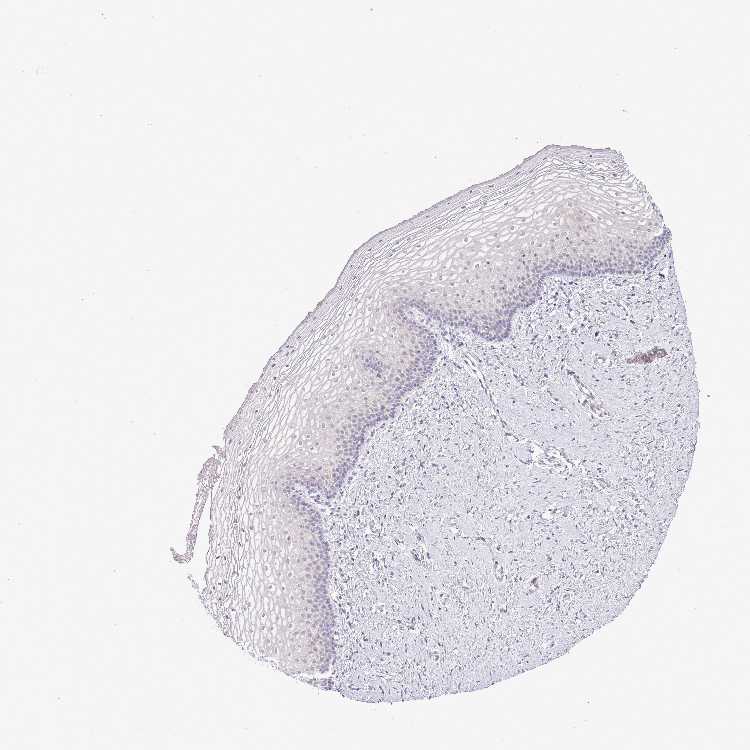

TISSUE PRIMARY DATA VAGINA Show tissue menu

Vagina

VAGINA - Antibody stainingi

Antibody staining in the annotated cell types in the current human tissue is reported as not detected, low, medium, or high, based on conventional immunohistochemistry profiling in selected tissues. This score is based on the combination of the staining intensity and fraction of stained cells.

Each image is clickable and will lead to virtual microscopy that enables deeper exploration of all samples and also displays staining intensity scores, fraction scores and subcellular localization as well as patient and tissue information for each sample.

Antibody HPA043270Antibody HPA047226

Squamous epithelial cells LowMedium